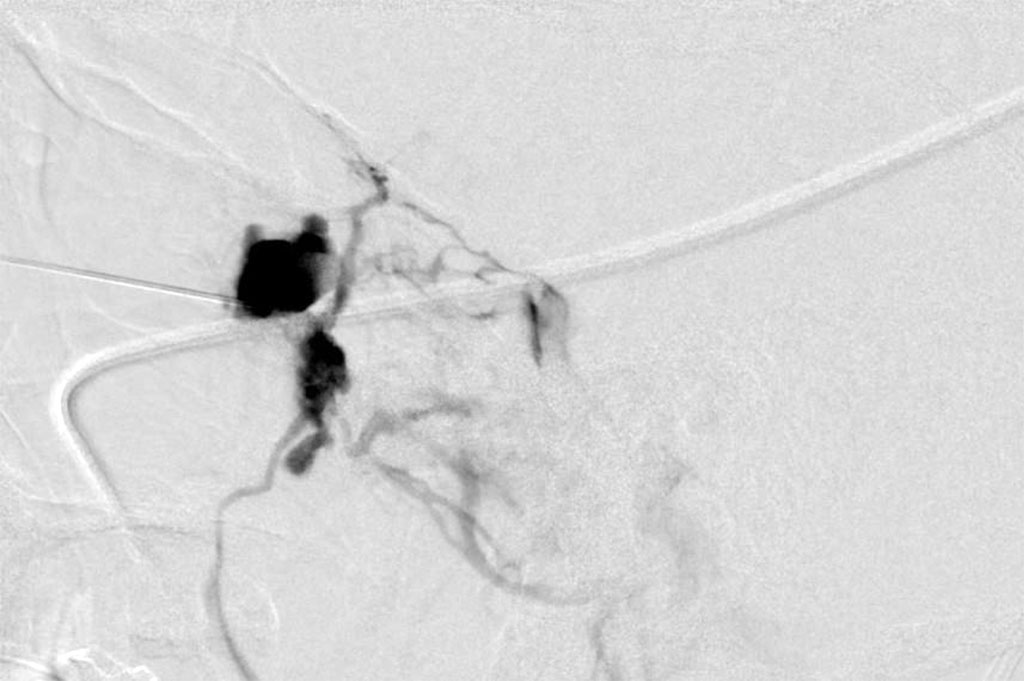

An endoscopic biopsy was performed and pathology revealed a low flow venous malformation. The patient was about to begin a round of fertility treatments soon. When discussed with her treating physician, there was a suspicion that excessive hormones and pregnancy could potentially cause an increase in the size of this lesion. Additionally, if needed, surgical intervention may not be possible due to the risks associated with advanced pregnancy. After some deliberation, it was decided to treat the lesion with sclerotherapy. Sodium tetradecyl was injected percutaneously under fluoroscopic guidance into the lesion in an uneventful procedure. (Figure 3)

Figure 3: Sclerotherapy – showing sclerosing agent in the vessels of the lesion